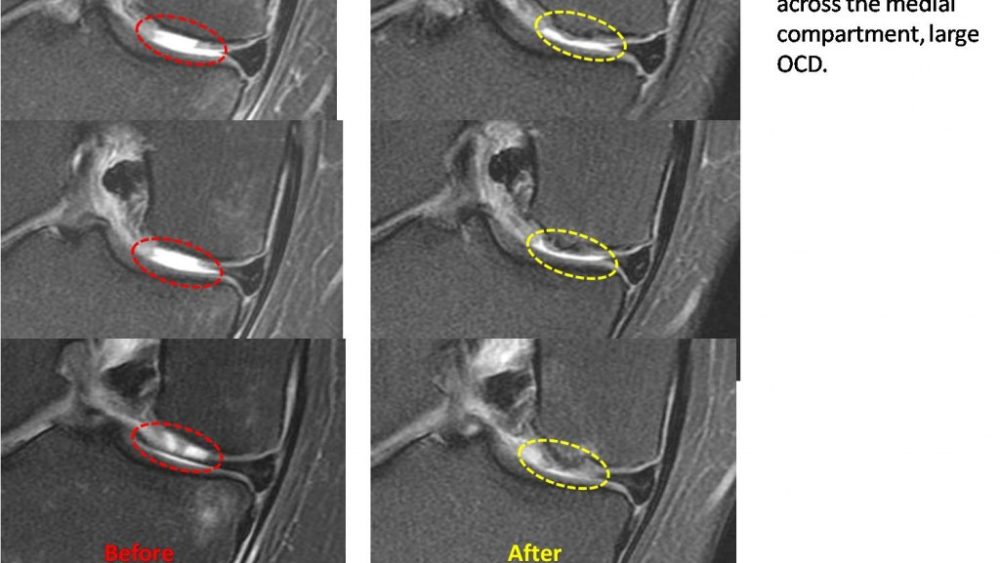

More than 2 years and still kicking…

A doctor discusses the long term outcome of stem cell injections for a knee osteochondral defect (OCD) or hole in the cartilage.